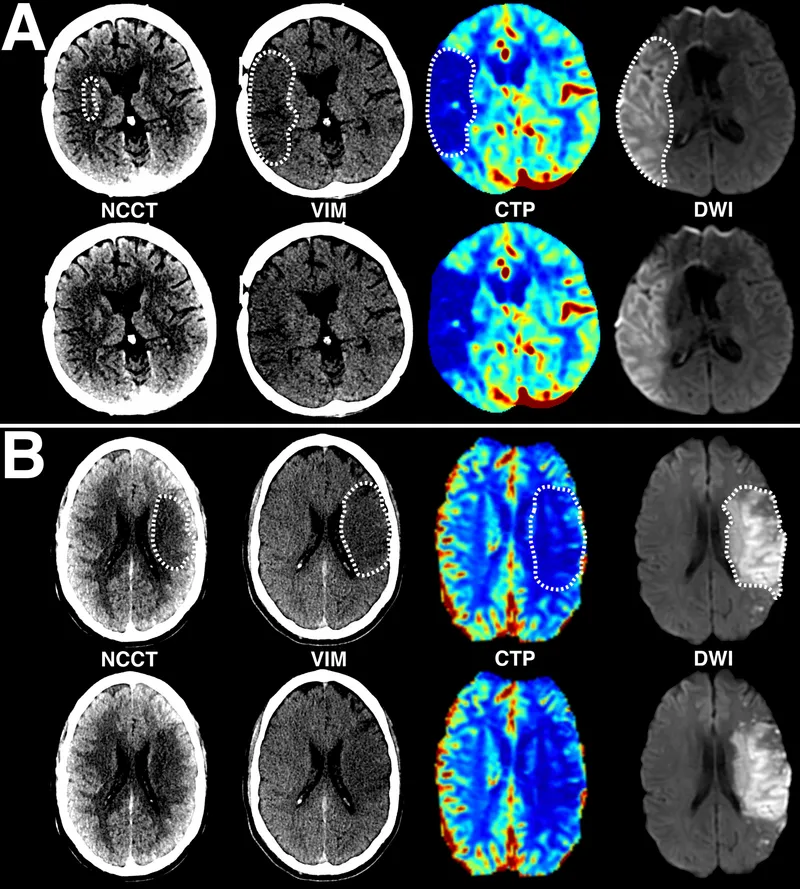

Initial Protocol: Immediate Non-Contrast CT (NCCT) is the critical first step to differentiate ischemic vs. hemorrhagic stroke. "Time is brain."

- NCCT is often normal in the first few hours but rules out a bleed before giving tPA. May show a hyperdense MCA sign.

- MRI with DWI is the most sensitive test for acute infarction.

- CTA/CTP is used to detect Large Vessel Occlusion (LVO) and assess the ischemic penumbra, guiding thrombectomy.

⭐ The ASPECTS score (0-10) on initial NCCT helps quantify early ischemic changes in the MCA territory to predict outcomes and guide therapy.